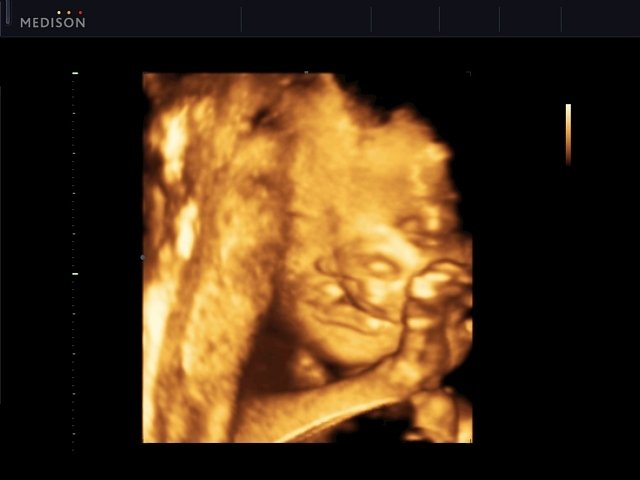

Cleft palate - defect of fetal`s development, 3D (echogramm №546)

[RU] Ultrasound image №546: Cleft palate (3D mode) - defect of fetal`s development.

Echogramm was received by ultrasound scanner SonoAce-R7 (out of production).